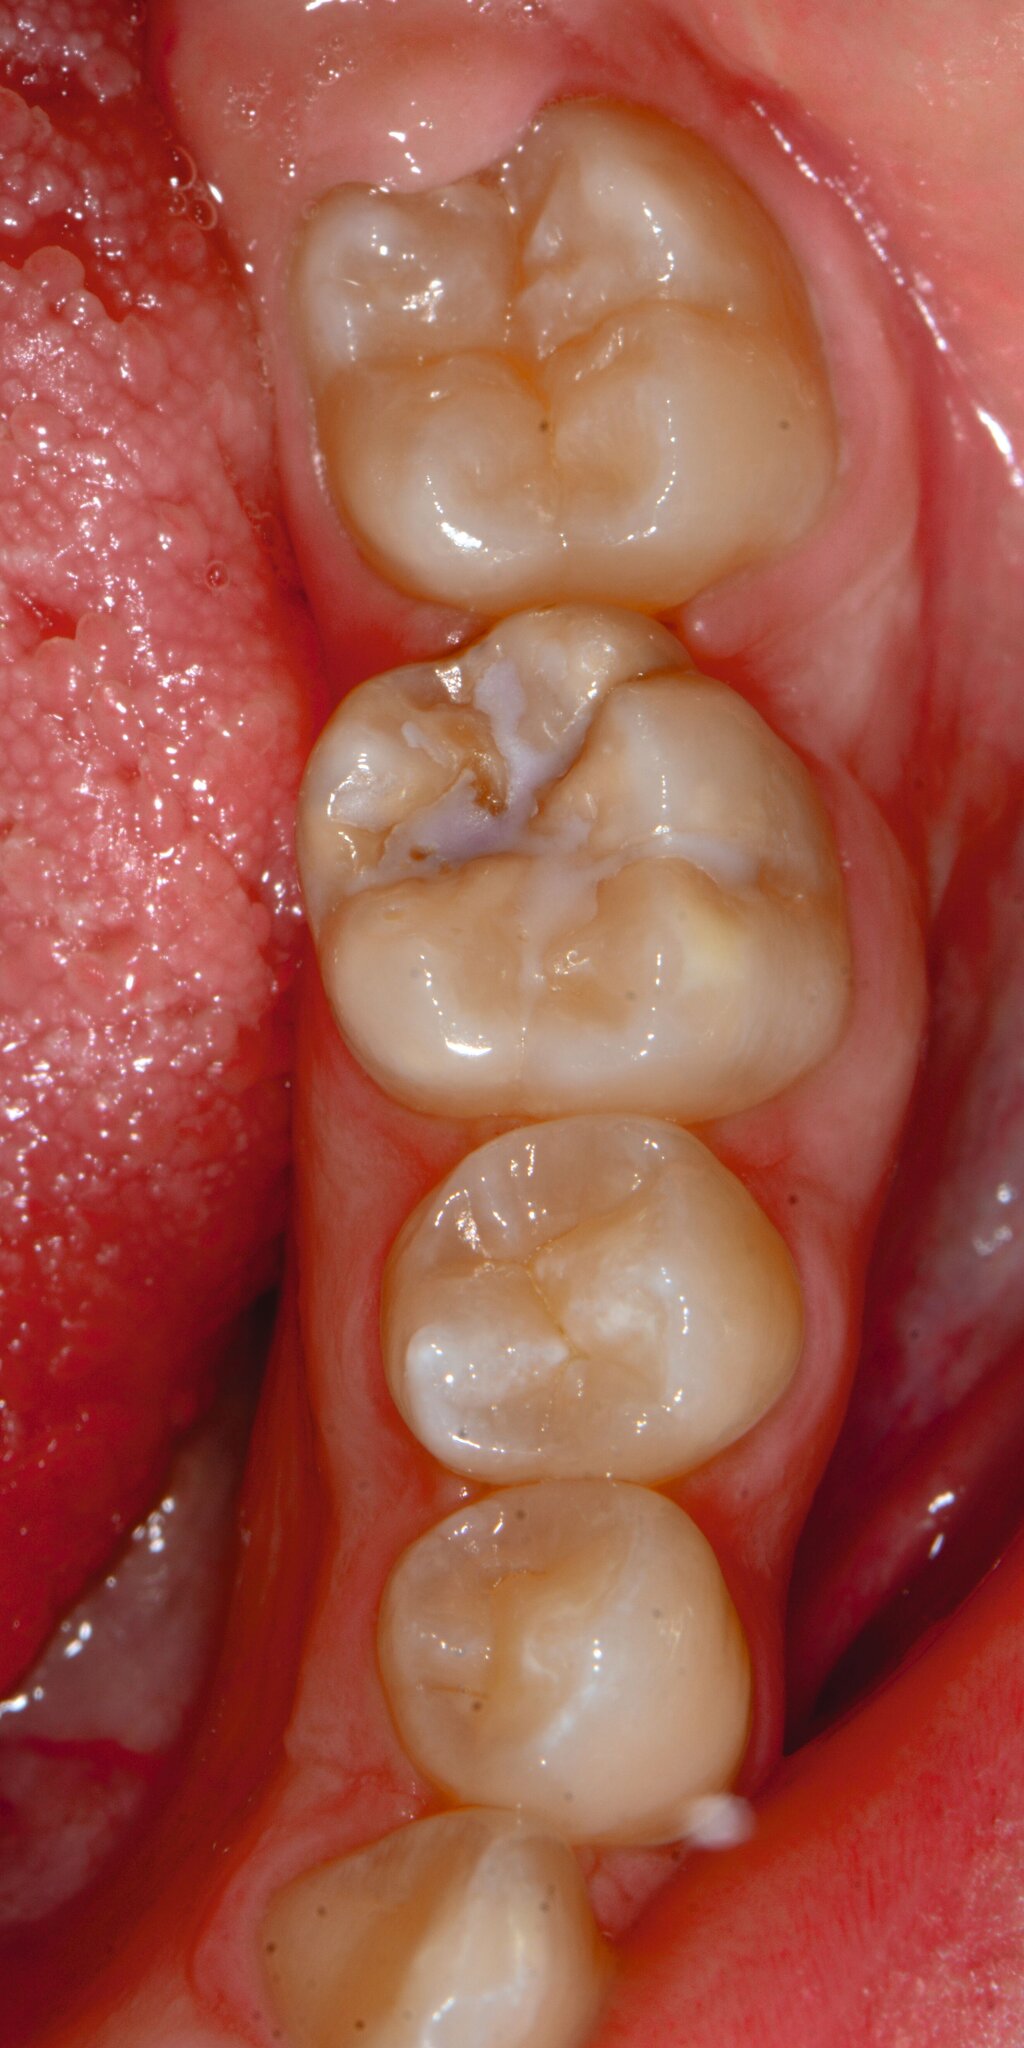

Bei post- beziehungsweise präeruptiven Oberflächendefekten ergibt sich in einigen Fällen die Indikation zur Restauration dieser MIH-Zähne. Unter Verweis auf die Lokalisation von MIH-bedingten Hypomineralisationen außerhalb der typischen Kariesprädilektionsstellen – zum Beispiel okklusale Fissuren und Grübchen oder Approximalflächen – werden diese als „atypische Restaurationen“ (engl.: „atypical restoration“, Abbildung 6) klassifiziert. Als ein weiteres Erkennungsmerkmal gilt die Präsenz von Hypomineralisationen im Bereich der Restaurationsränder. MIH- und kariesbedingte Restaurationen können und sollten sicher voneinander abgegrenzt werden.

Für die Dokumentation und Klassifikation der MIH wurden verschiedene Systeme vorgeschlagen. Als historisch und veraltet gilt der (modifizierte) DDE-Index. Demgegenüber haben die Kriterien der EAPD – abgegrenzte Opazitäten (Abbildung 3 und 4), Schmelzeinbrüche (Abbildung 5), atypische Restaurationen (Abbildung 6) – mittlerweile die weiteste Verbreitung gefunden. Diese wurden 2003 erstmals zur Beschreibung der MIH auf empirischer Basis publiziert [Weerheijm et al., 2003] und den Jahren 2010 und 2022 im Rahmen der damaligen MIH-Workshops bestätigt [Lygidakis et al., 2010; 2022].